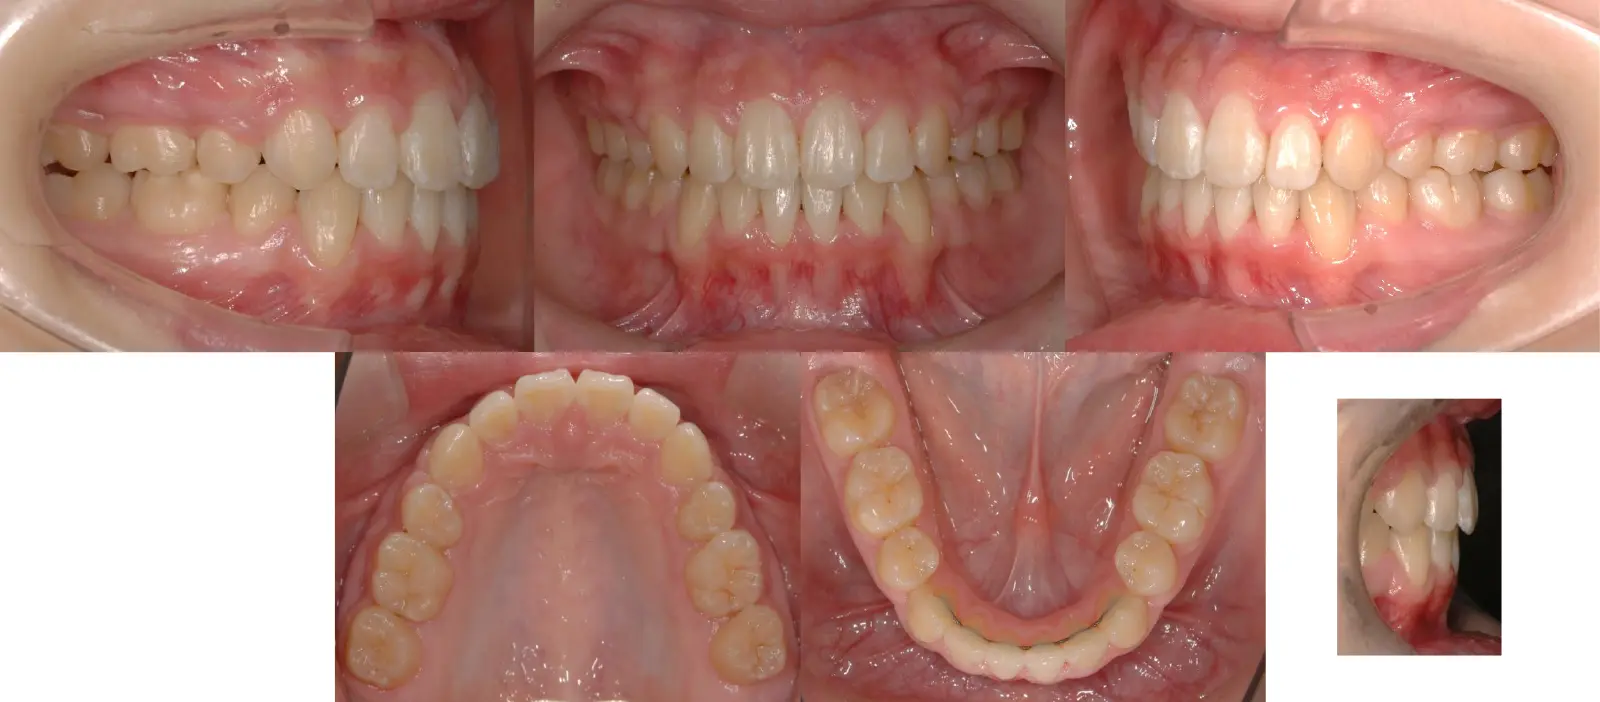

アングルⅡ級 叢生を伴う上顎前突症

- 主訴

前歯がかみ合わない、突出している

- 年齢

10代

- 治療期間

1年4ヶ月

- 治療回数

14回

- 治療に用いた主な装置

カスタムメイド型マルチブラケットタイプのデジタル矯正装置(インシグニア)

TAD(ミニスクリュー)を上顎臼歯部に植立

- 治療費

600,000円(税別)、調整料5,000円(税別)

※伊那分院にて治療

- 抜歯部位

上下顎第一小臼歯 計4本